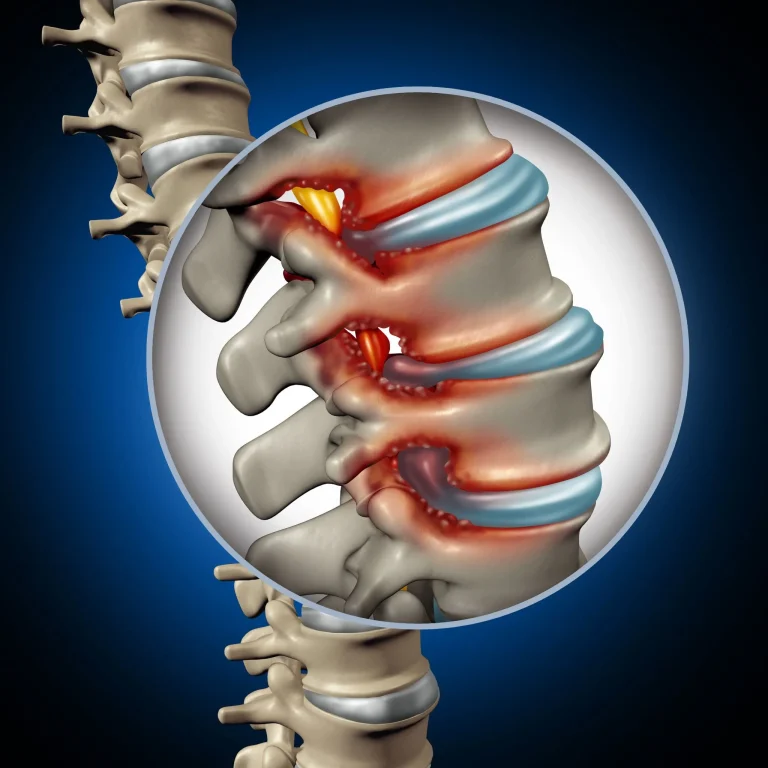

Illustration of a spinal column highlighting inflammation and nerve compression.

Residual Stenosis

Stenosis persists or reoccurs commonly after discectomy, requiring additional decompression surgery.